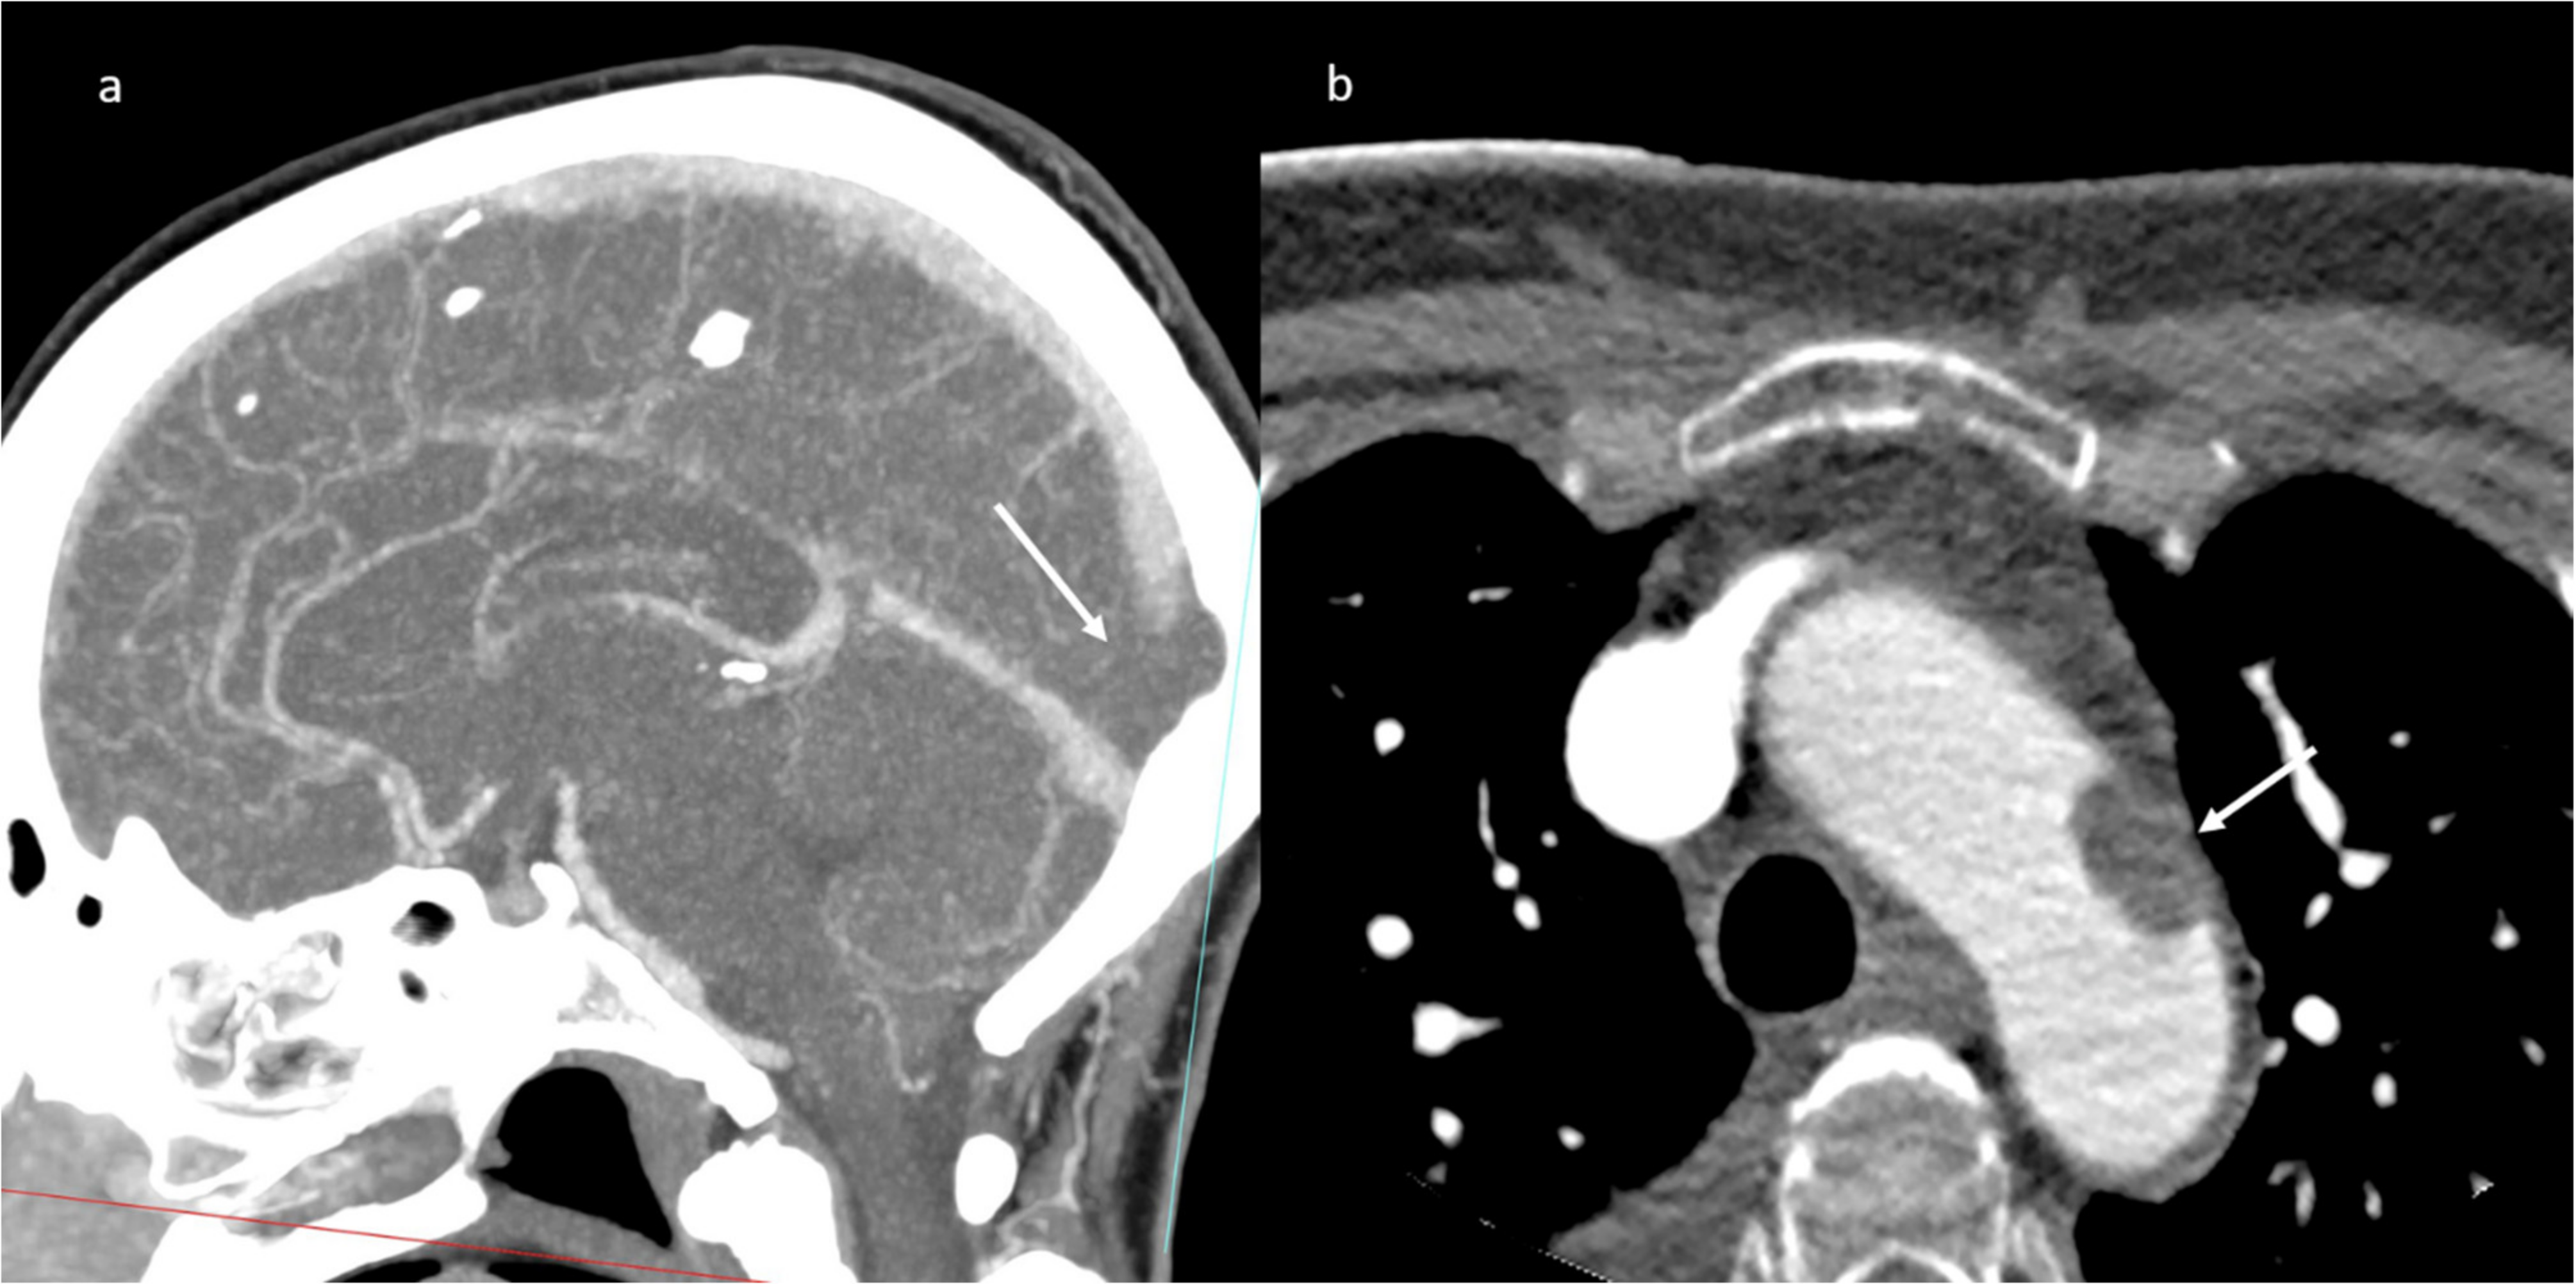

A brain computed tomography (CT) scan showed multiple subacute intra-axial hemorrhages in atypical locations, including the right frontal and the temporal lobes (Figure 1), with ipsilateral hemorrhagic subarachnoid suffusion, raising the suspicion of Labbè/superior longitudinal sinus thrombosis, even if brain angio-CT demonstrated only a non-occlusive thrombosis of the vein of Galen (Figure 2a), but also a floating thrombus within the aortic arch (Figure 2b).

Figure 2.

CT-angiography: partial thrombosis of the vein of Galen (a); presence of a floating thrombus within the aortic arch (b).